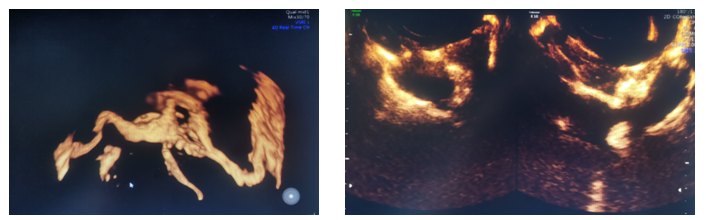

患者为31岁不孕症女性,在西咸院区产科就诊后,临床医生接诊后认为需要超声检查以评估宫腔情况及双侧输卵管通畅性。超声诊断中心任媛主治医生全程配合,为患者行四维超声宫腔成像及输卵管超声造影检查,整个过程顺利,耗时短,患者无不适,该项检查为临床及患者提供了客观影像学信息。

输卵管超声造影检查是通过向宫腔内注射超声造影剂,使宫腔及输卵管显影,可清楚观察到宫腔、宫角、双侧输卵管的形态及与卵巢的位置关系,五楼自拍